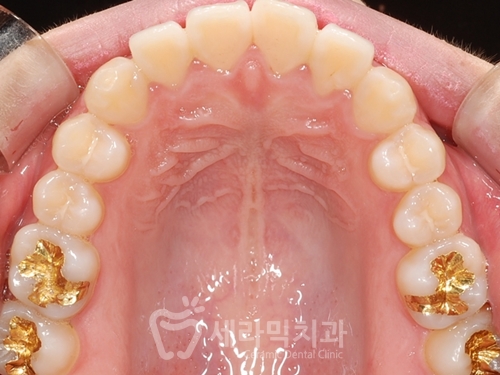

(1) 문제점 진단

치아돌출 뿐 아니라,

잇몸돌출이 동반되어 있는 걸 확인할 수 있으며

얼굴 옆 라인을 보면

돌출입과 함께, 턱선이 밋밋한

'무턱' 경향을 보여줍니다.

치아의 배치 자체는 고른 편이나,

치아가 전체적으로 바깥 쪽으로 뻗쳐있습니다.

(2) 치료계획

치아돌출과 잇몸돌출이 동반된 돌출입이라

치아 4개 발치를 통해 돌출입을 개선합니다.

옥니가 되지 않도록

상악에는 하이토크 브라켓을 사용합니다.